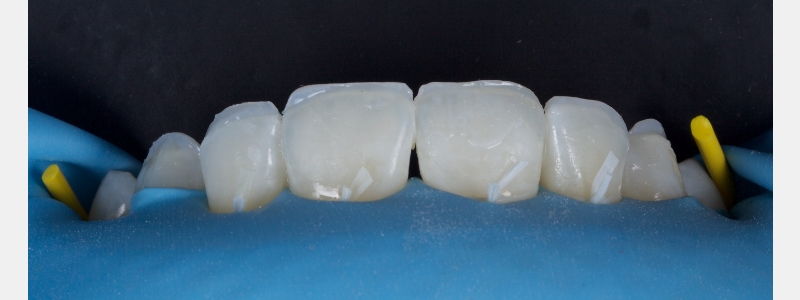

A diagnosis of altered passive eruption (APE) alongside tooth surface loss (TSL) secondary to parafunction was made for a referred female patient in her early 20s who complained of having“short, fat, baby teeth.” Due to her age, she was treated with a simple gingivectomy (after bone sounding), nightguard vital bleaching (NGVB), and additive edge bonding.

The worn incisal edges were restored with edge bonding, a new technique for restoring worn dentition. This should be regarded as a multiple Class IV restoration.